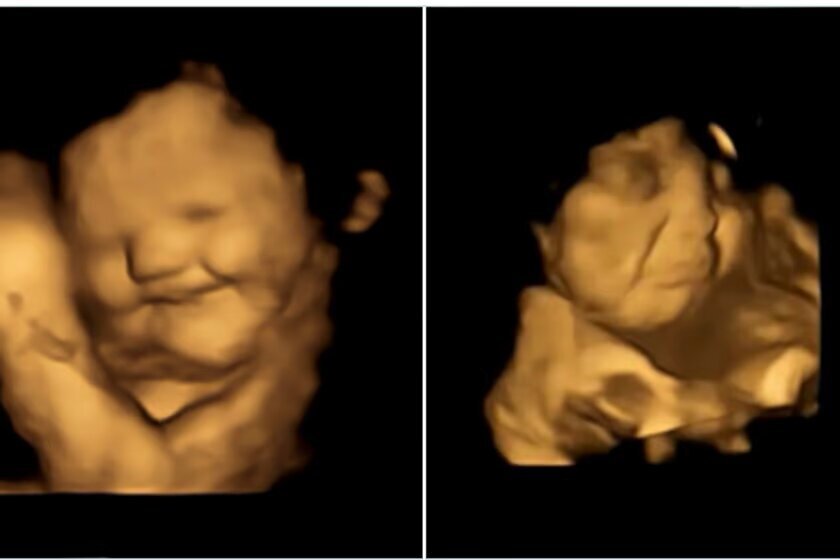

На удивительных кадрах полученных при помощи УЗИ, хорошо видно, как будущие детки с отвращением морщат лица через несколько минут после того, как мать съела горькую капусту, или улыбаются, когда до них добегает сладкий вкус моркови.

Иллюстрация Beyza Ustun et al. / Psychological Science, 2022.

Чтобы проверить гипотезу, исследователи использовали так называемую 4D-ультразвуковую технологию, ценному способу визуализации движений плода с высокой детализацией. Участие в эксперименте приняли 100 матерей, все в последнем триместре беременности.

Невероятные результаты показали, что у деток, которым "скормили горькую капусту", было больше реакций в виде "плачущего лица" по сравнению с плодами, которым "скормили" сладкую морковь. Последние чаще меняли выражение лица на "смеющиеся лица".

В контрольной группе плод более последовательно демонстрировал нейтральные лица, так как не подвергался воздействию какого-либо вкуса. (Тут поясним, что дети в утробе могут "выдавать эмоцию" и по другим поводам,

как бы спонтанно улыбаясь.)